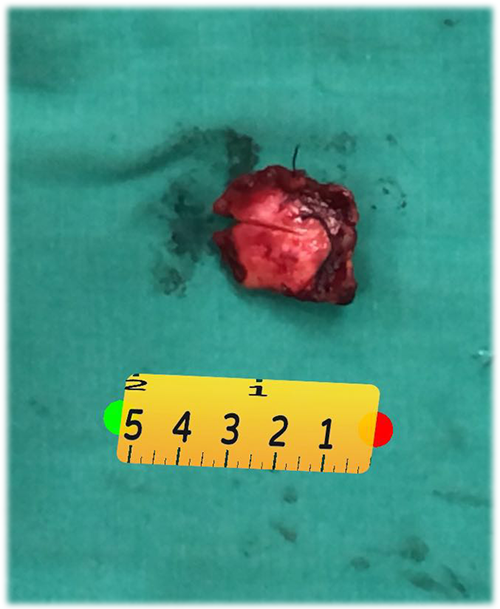

右肝肝癌---右肝肿瘤切除